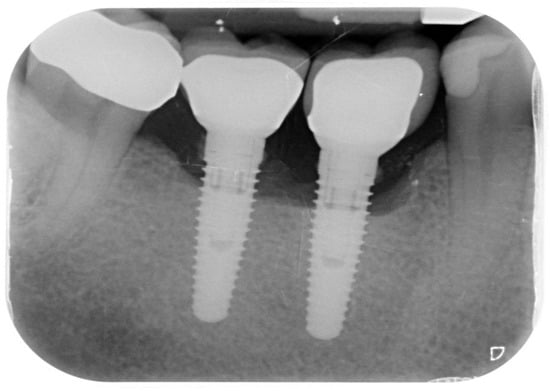

Peri-Implantitis: Application of a Protocol for the Regeneration of Deep Osseous Defects. A Retrospective Case Series

3. Results